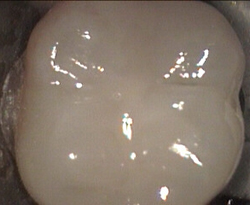

Top of back tooth

Unusual prevalent but superficial groove pattern on permenant molar after Sealed